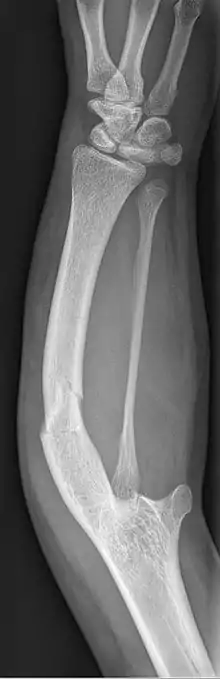

| Ulnar hypoplasia | |

Ulnar dysplasia also known as ulnar longitudinal deficiency, ulnar club hand or ulnar aplasia/hypoplasia is a rare congenital malformation which consists of an underdeveloped or missing ulnae bone, causing an ulnar deviation of the entire wrist. The muscles and nerves in the hand may be missing or unbalanced. In severe cases, ulnar digits (e.g. ring and pinky finger) may be missing. Sometimes, radial dysplasia occurs alongside this malformation.[2] This condition occurs in 1 in 100,000 live births.[3][4][5][6] Sometimes, other orthopedic problems occur alongside this malformation, such as scoliosis.[7]

Type 1: The mildest type of ulnar dysplasia. The ulnae is slightly shorter than average and there is a barely noticeable wrist deviation

Type 2: The ulnae is moderately-severely smaller than normal. The radius is deviated and so is the hand

Type 3: The ulnae is completely missing. The radius is even more deviated, causing a severe ulnar deviation of the hand.

Type 4: The most severe type of ulnar dysplasia, the ulnae is completely missing, and the wrist is severely deviated. The elbow bones are fused together, so the elbow has reduced mobility